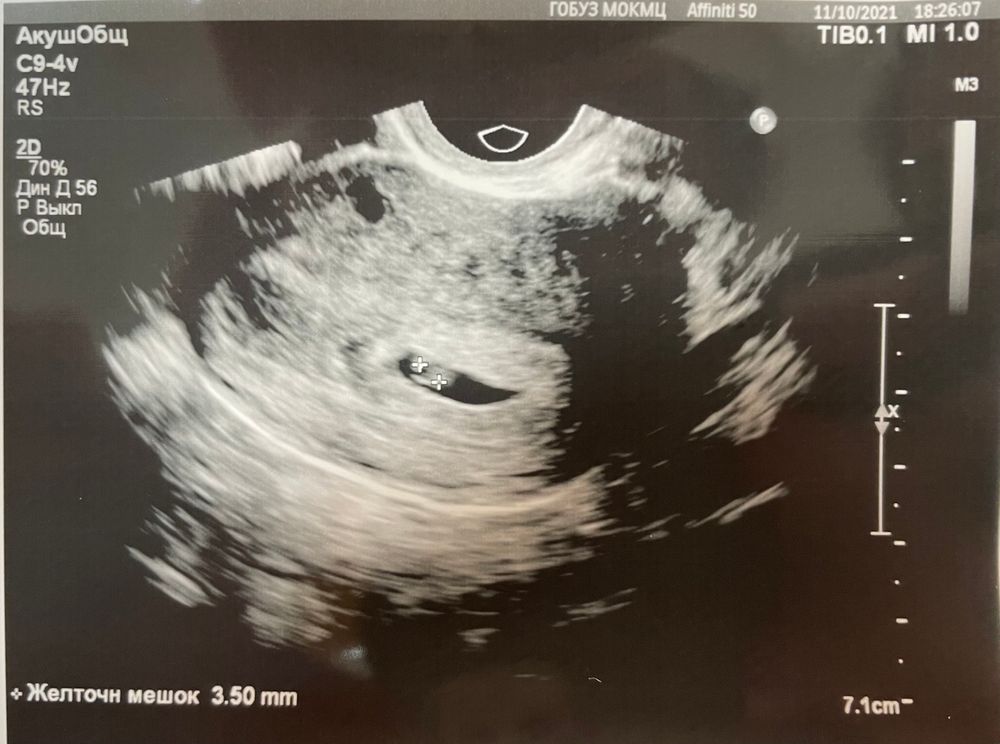

Узи на 20 дпо

Беременность- 1 триместр ( только до 10 недель)Девочки, кто был на узи на 20 (+/-) дпо, что на таком сроке удалось рассмотреть? Может у кого под рукой фото узи есть. Интересно как там все развивается, и когда лучше идти, что бы понять маточная ли беременность☺️☺️☺️

Я была на узи ~ на 18 дпо (4 недели 4 дня) и ничего не увидели, даже малюсенькую точечку, а через 2 недели ровно нашли креветочку)

Анютка, будет примерно так) вам уже скажут где прикрепился, посчитают сосуды в пуповинке, измерят хорошее СБ и тд) вот тогда вы получите удовольствие без накрутки нервов и выжидания недели, чтобы нашли точно, ибо нервов сожжете кучу)